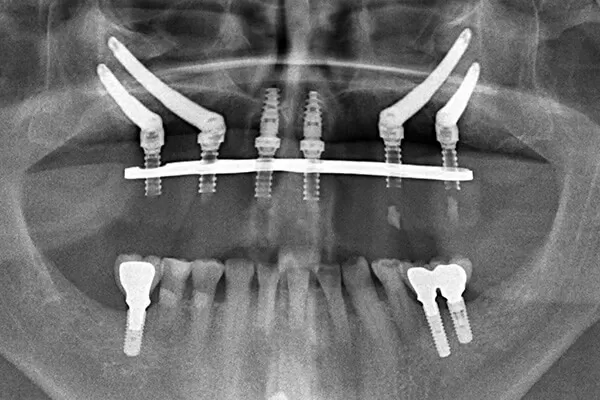

Hãng Nobel Biocare một lần nữa đã nghiên cứu và đưa ra giải pháp dùng Zygoma Implant để gắn Implant vào xương gò má để giải quyết được những trường hợp mất răng toàn bộ ở hàm trên với thiếu xương nghiêm trọng do xoang hàm lớn, vùng xương ổ răng bị tiêu xương trầm trọng.

Với sự khảo sát bằng CT Cone Beam trước phẫu thuật cùng đội ngũ BS kinh nghiệm về phẫu thuật trong miệng & hàm mặt, đội ngũ Bác Sỹ phục hình & kỹ thuật viên labo và sử dụng hệ thống Zygoma Implant duy nhất trên thế giới của Nobel-Biocare sẽ là những điều kiện cần thiết để thực hiện kỹ thuật vượt trội này.

Những thành công của Zygoma Implant đã được báo cáo tại các hội nghị Implant thế giới và các tạp chí y học quốc tế.

Lần đầu tiên ở Việt Nam, Kubet - Ku Casino đã và đang đưa vào kỹ thuật này và áp dụng tại trung tâm. Chúng tôi hy họng và tin tưởng sẽ giúp ích được nhiều hơn cho các bệnh nhân mất răng toàn bộ ở hàm trên đã bị từ chối việc cắm Implant vì lý do thiếu xương trầm trọng trước đây.